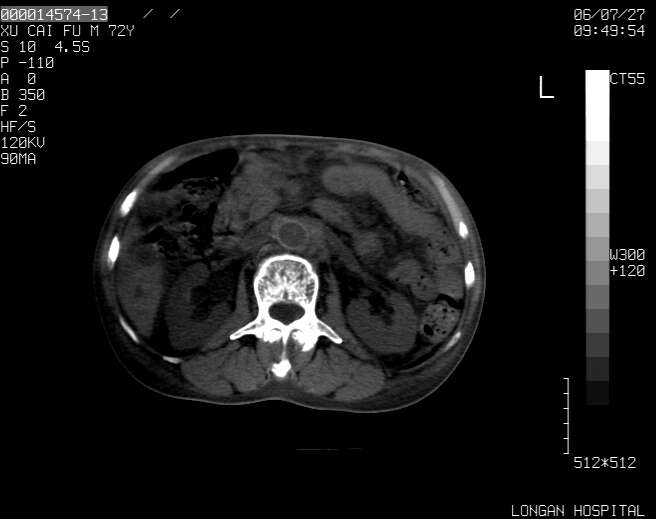

以下是引用winter在2006-7-30 20:14:00的发言:[br]1、考虑胆囊癌伴胆道侵犯并高位胆道梗阻、肝内多发转移、腹膜后淋巴结转移。[br]2、右肾轻度积水。[br]3、老人家72岁了胰腺头体尾部均较饱满,不过未见密度异常及其他异常征象。[br]4、腹水。

以下是引用jiajie在2006-7-31 7:10:00的发言:[br]考虑肝转移瘤,腹膜后淋巴结增大。[br]胃癌不能除外,建议胃镜检查。